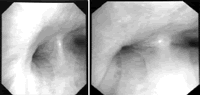

辅助检查 肝肾功能无异常,免疫系统各项指标(-),血总IgE水平正常,心电图(-)。血气分析正常。纤维支气管镜检查示:主气管及各级支气管黏膜充血、水肿,可见大量分泌物,主气管下段、双侧主气管及双侧各级支气管可见呼气相明显狭窄,左肺上叶及右中叶支气管开口狭窄(图1)。

纤维支气管镜检查提示气管及支气管呼气相塌陷,诊断不除外复发性多软骨炎(RP),再查体发现鼻梁塌陷。询问病史,鼻梁塌陷在近1年内明显。复阅胸部 CT发现,呼吸相,主气管较正常人气管明显缩窄,左右支气管分叉显示内径明显狭窄(图2)。